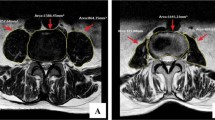

Wedge-shaped changes occurred in single lumbar vertebrae by X-ray and CT, as well as high signal changes by MRI T2WI. All patients had informed consent and signed the informed consent form. Moreover, all methods were carried out in accordance with relevant guidelines and regulations issued by the General Hospital of Northern Theater Command. All experimental protocols were approved by the General Hospital of Northern Theater Command approval committee.

The body surface grid locator was placed on the patient's damaged vertebrae before surgery (Fig. 1A). The fractured vertebrae and body surface location were reconstructed from a CT scan of the lumbar. In addition, we were required to import 3D reconstruction data by CT into Mimics 21.0 software (Materialise company, USA), applying a new mark to label the injured vertebrae and grid locator as well as fulfilling the reconstruction of vertebrae and grid locator (Fig. 1B,C).

(A) Key puncture points of preoperative mesh optimization. (B) X-ray fluoroscopy showing the intersection of the midpoint of the line between the upper and lower endplates of the vertebral body and the tangent of the lateral edge of the pedicle of the vertebral body. (C) X-ray fluoroscopy to determine the target point in the vertebral body, where the tip of the guidewire reached the inner edge of the contralateral pedicle. (D) X-ray fluoroscopy showing the tip of the guidewire reaching the anterior edge of the vertebral body.

Cylinders replaced puncture channels after repair. The cylinder's end was placed at point C, where the extension line of the contralateral pedicle's inner border meets the vertebral body's anterior edge. After that, we had to swing the other end, which was set at point B, the midway of the line between the vertebral body's upper and lower endplates and the tangent line of the pedicle's lateral edge, which horizontally transverses it. The pen-marked skin piercing point is A (Fig. 1D).

The prone patient was given local anesthesia (lidocaine with a dose of 50–100 mg per patient), sterilized, and punctured at the preoperatively planned skin puncture spot (point A) (Fig. 2A). We found the spinal bone puncture point by "C" arm X-raying the "outside edge of the pedicle" and the transverse process's tangent line (point B, Fig. 2B). The core is removed, and the guidewire is implanted when the puncture needle tip reaches the inner pedicle. The guidewire tip touches the vertebral body's anterior edge and the contralateral pedicle's inner edge at the target site (point C, Fig. 2B). After checking the puncture path and crucial puncture spots, we inserted the working channel and applied bone cement.